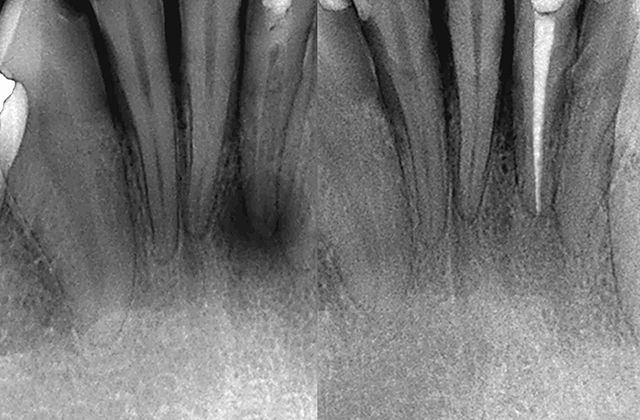

More InfoRoot Canal Therapy

Root Canal treatment can save a tooth from extraction and relieve pain caused by inflammation and infection